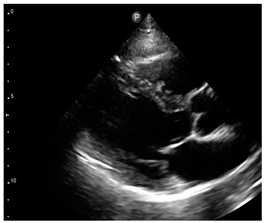

Compared to those who develop HFpEF, clinical HFrEF develops generally through disproportionate myocyte loss rather than hypertrophy (Figure 1) [49].

Figure 1.

Proposed mechanism for the progression of hypertensive heart disease to heart failure patterns, LVH: left ventricular hypertrophy, LV: left ventricular, HFpEF: heart failure with preserved left ventricular ejection fraction, HFrEF: heart failure with reduced left ventricular ejection fraction.